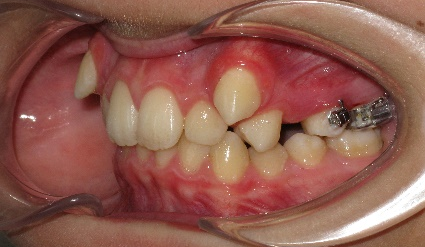

В полости рта: смыкание первых моляров по дистальному типу. Сужение зубных рядов в боковых отделах. 13 и 23 - вестибулярное и супраположение с дефицитом места в зубном ряду на величину ширины коронки клыка. Глубокая резцовая окклюзия.(рис.2.)

Рис.2.Смыкание зубных рядов пациента А. до лечения и окклюзионный вид.